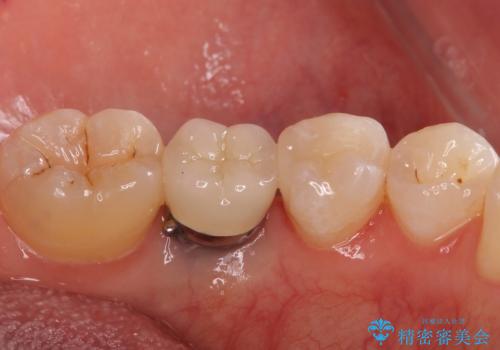

- 下の奥の銀歯を白くしたいとのことで来院されました。

セラミックインレーでの治療を行いました。

- 左下5 セラミックインレー 77,000円費用は治療当時の料金となります

銀の詰め物のやり替えは2回の来院で終わらせることができます。

下の歯は口を開けたときに外からよく見えるため、セラミックにやり替えることで印象が大きく変わります。